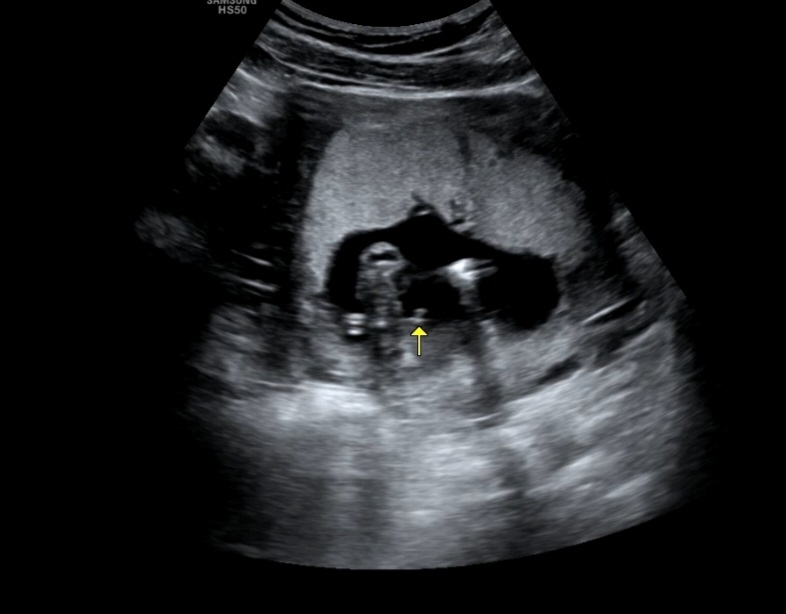

14주 6일 아들맘일까요?

같이 봐주세요! 탯줄이거나..딸일 가능성은 없을까요..